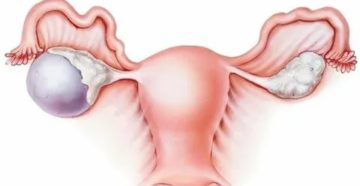

Шоколадная киста яичника — как лечить, причины и симптомы болезни Под названием эндометриодная (шоколадная) киста…